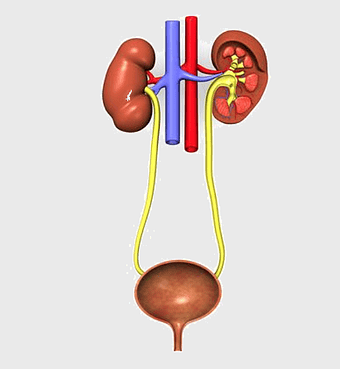

urinary system anatomy, kidney function illustration, ureter diagram, bladder infection symptoms, renal system health, excretory function chart, genitourinary medical diagram -